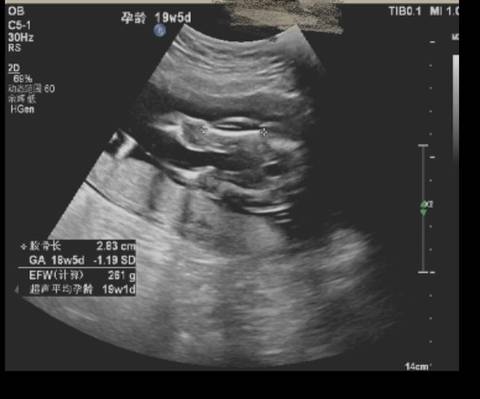

B超照到的股骨,大家看看是不是女孩

journal_insert_pic_1684206292

亲爱的,通过这些判断不出来是什么样性别的哈,反正宝宝发育好就是最好的哈,祝你好孕。

你好。我们是判断不了男宝宝跟女宝宝的,孕期定期检查,我觉得宝宝健康就好的。祝心想事成 。

其实现在只要宝宝健康就可以了,其他顺其自然吧,男宝女宝都是很可爱的,不过也能理解,一般都会有好奇心的啦。

亲,我们都是一样觉得好奇,确实没什么依据,不要想太多,生下来最准确的,心想事成!